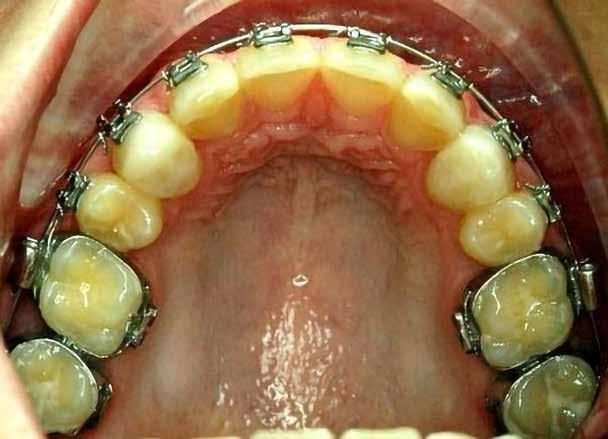

sok korrigálása, valamint az impaktálódott fog előtöréséhez szükséges hely megteremtését követően, egy merev acél ív segítségével stabilizáltuk a fogakat. Ezt követően elvégeztük a jobb felső nagymetszőfog sebészi feltárását. A fog koronáját csupán lágyrész borította, ezért nem volt szükség a csontállomány elvételére. A felszabadítás során egy 975

nm-es hullámhosszon pulzáló üzemmódban alkalmazott lézert használtunk (LaserHF standard, Hager & Werken). A teljesítménye 3 W, az aktív ciklus-idő 50%-os, a vezetőszál átmérője pedig 0,4 mm volt (2. ábra). A lézert 150 másodpercen keresztül alkalmaztuk. A fogat borító lágyrészek eltávolítását követően egy láncos brekettet rögzítettünk a metszőfog bukkális felszínére. A műtétet követően nem tapasztaltunk vérzést, nem alakult ki oedema, valamint a páciens sem számolt be fájdalom vagy bármely egyéb kellemetlenség fennállásáról. A felszabadítást követően a páciens minden hónapban háromszor jelent meg a felszabadított területre ránövő lágyrészek és az íny lézeres eltávolítása céljából. A beavatkozások során ugyanazt a lézer készüléket használtuk, mint amivel a felszabadítást végeztük. Közvetlenül a felszabadítást követően megkezdtük a fog finom extrudálását a láncos breketthez kötött füzérgumi segítségével.

6 hónapon keresztül tartott. Ennek megfelelően a fog körül található szövetek a felszabadítás, valamint a havi kontrollok során 975 nm-es (több mint 25 J/cm2 energiasűrűség) és 660 nm-es hullámhosszúságú (12–18 J/cm2 energiasűrűség) lézersugarakkal is megvilágításra kerültek. Az impaktálódott fogat megközelítőleg 7 hónap alatt tudtuk megfelelő pozícióba mozgatni (3. ábra). Az orthodoncia kezelés aktív szakasza 18 hónapon keresztül tartott. A fogívek végső nivellálását és a fogak végleges pozícióba rendezését 0.018 × 0.025-ös acélívekkel végeztük.